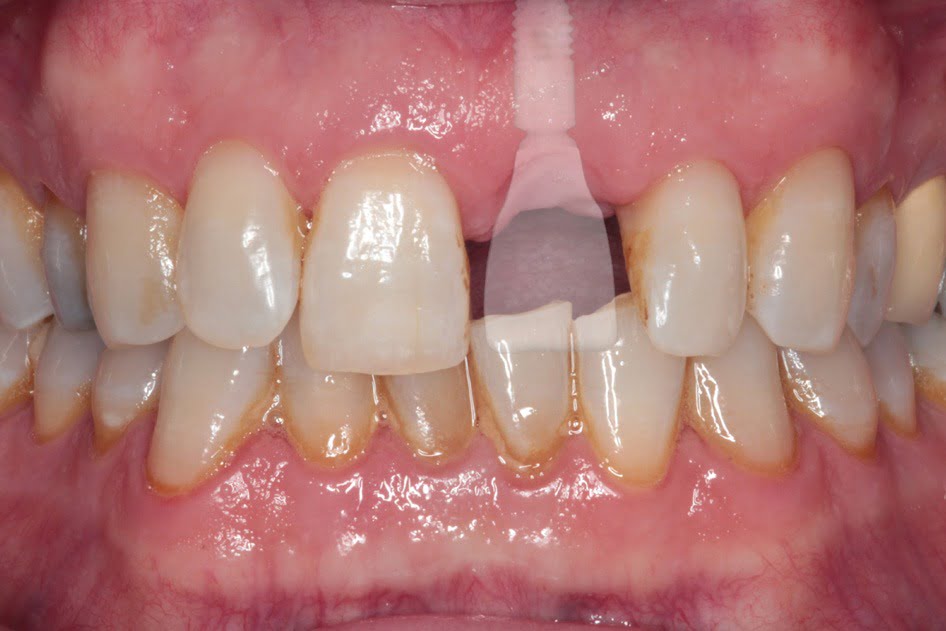

Dental implants are artificial teeth that provide long-lasting replacements for missing or failing teeth, and can be used to secure dentures.

Dental implants have a number of advantages over more conventional methods of replacing missing teeth. An implant-supported crown is very similar to your natural tooth because it is fixed permanently, and does not need your other teeth or soft tissues for support.